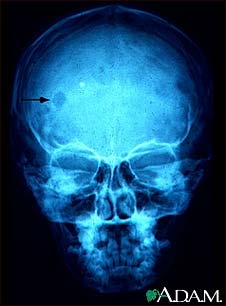

Eosinophilic granuloma - X-ray of the skull

This x-ray of the skull shows an eosinophilic granuloma (a lesion made-up of a type of white blood cell). This condition can range from a single eosinophilic granuloma to massive infiltration of skin, bone, and body organs.